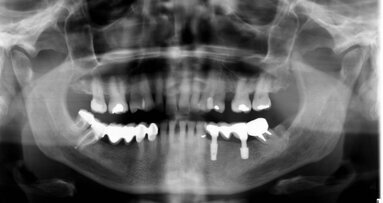

A 19-year-old male reported with a missing maxillary right central incisor. The patient gave history of trauma due to accident, which resulted in the loss of the maxillary right central incisor. On clinical examination, deficiency in the anterior residual alveolar ridge with loss of buccal cortical plate was noted. The patient was in good health and was a non-smoker with no medical contraindications for surgery, had excellent oral hygiene and a strong desire to restore the area with a fixed prosthesis. On examination there were no clinical signs of periodontitis and dental caries. Radiographically, the clinical findings were verified and revealed vertical and horizontal bone loss that was limited to the maxillary right central incisor (Fig. 2) Using the native software, non-distorted measurements were made on the cross-sectional slices to determine the dimensions of the defect within the residual socket site, and lack of facial cortical-plate as confirmed in the axial view.

A local anaesthetic agent was administered in the area of the maxillary right upper central incisor. An incision was made on the buccal and palatal aspect of the involved edentulous ridge and a full thickness flap was reflected from the maxillary right lateral to the maxillary left central incisor tooth to reveal the anticipated horizontal and vertical bone defect diagnosed with CBCT imaging (Fig. 3).